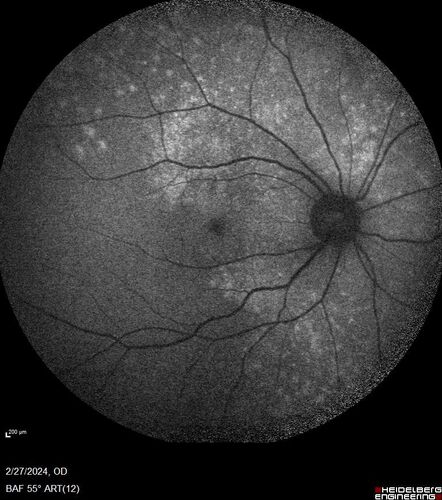

Syphilitic Chorioretinitis

41 year old man with vision loss for five days left eye. VA 20/32, 20/200

Syphilitic Chorioretinitis Both Eyes